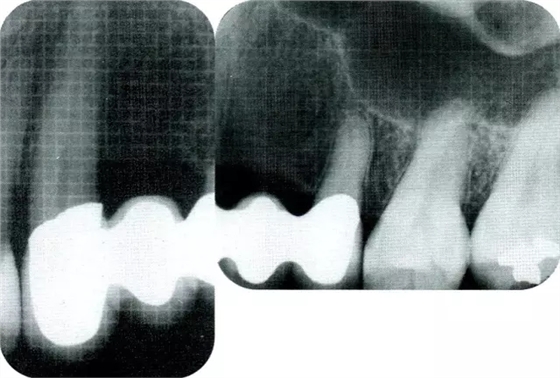

▲圖7-2術(shù)前x片。確認(rèn)存在垂直性深骨缺損。

▲圖7-7術(shù)前,術(shù)后的x片。確認(rèn)出現(xiàn)骨再生,牙槽嵴硬線。